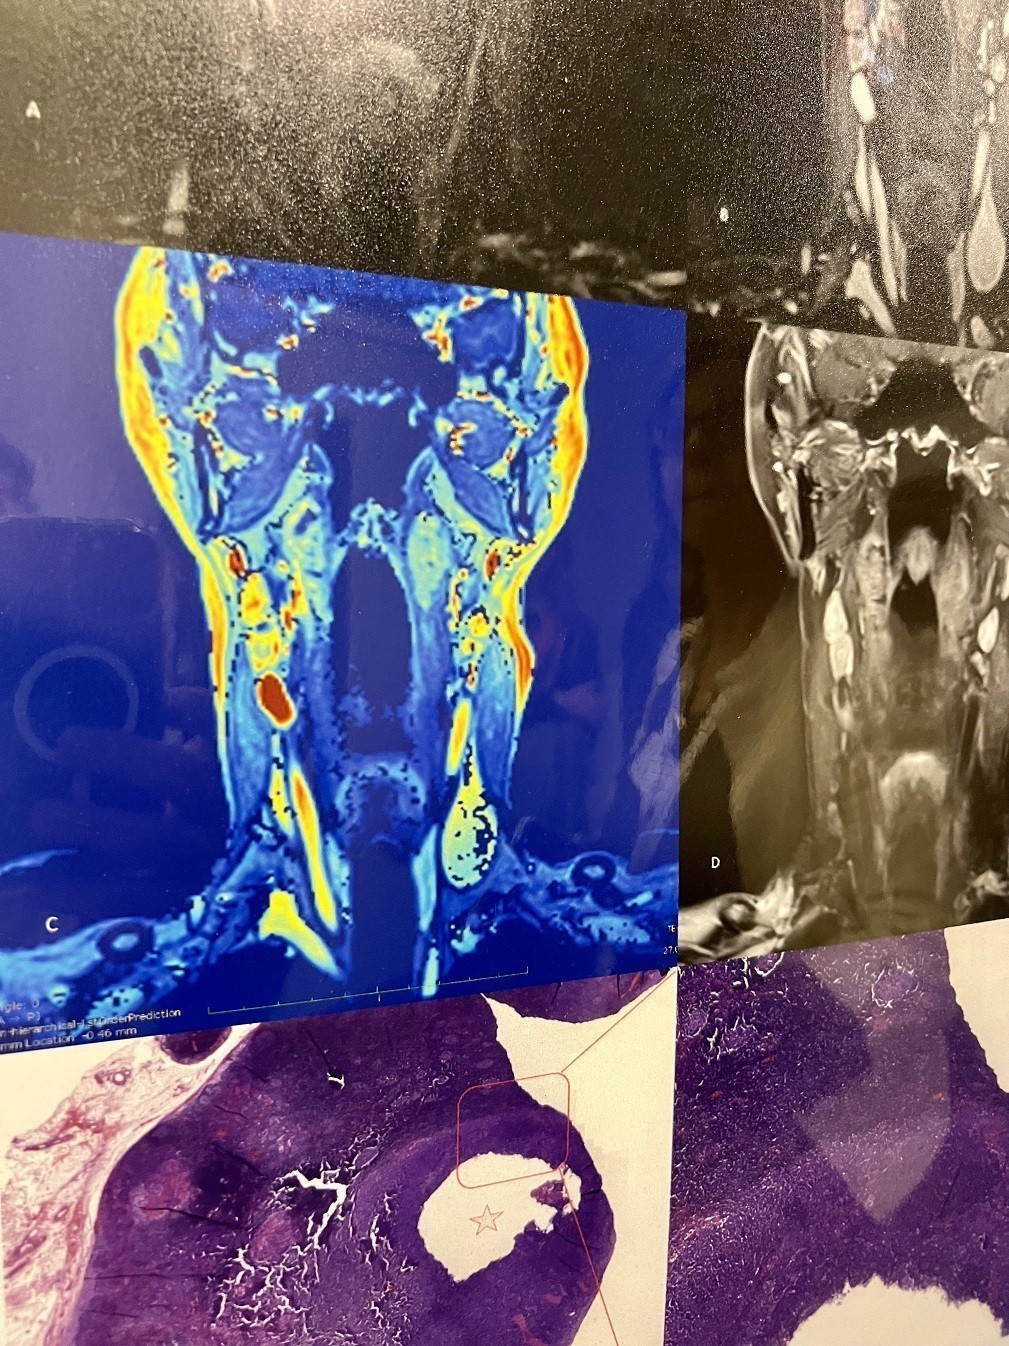

Προς το παρόν έχουμε χιλιάδες εικόνες υψηλής ευκρίνειας από το ανθρώπινο σώμα και αυτό είναι σημαντική εξέλιξη, επισημαίνουν οι επιστήμονες. Μάλιστα στο άμεσο μέλλον θα μπορούν να χειρουργούν με τη βοήθεια της «κινηματογραφικής ανατομίας» δηλαδή να παρακολουθούν με εξαιρετική λεπτομέρεια την περιοχή που επεμβαίνουν. Η τεχνολογία, ήδη μας βοηθά σε λιγότερο χρόνο να γίνονται περισσότερες εξετάσεις που δίνουν εικόνες εξαιρετικής ευκρίνειας από το ανθρώπινο σώμα, επισημαίνει ο Μ. May και εξηγεί πως η ΑΙ μπορεί να βοηθήσει – μέσω αλγορίθμου -τον ακτινολόγο να εντοπίσει έναν όγκο, και προσθέτει : «Τώρα βιώνουμε μια συναρπαστική εποχή, καθώς χτίζουμε υψηλής ανάλυσης δεδομένα, είμαστε η γενιά που αποθηκεύει αυτά τα δεδομένα. Δημιουργούμε αρχεία. Όμως, οι αλγόριθμοι θα πρέπει να τα επεξεργαστούν ώστε η επόμενη γενιά γιατρών να ωφεληθεί από αυτά τα προγράμματα που σήμερα ονομάζουμε ΑΙ».

Στον τομέα της διαγνωστικής και θεραπευτικής απεικόνισης, για παράδειγμα υπάρχουν πλέον εξελιγμένα μηχανήματα, όπως πρωτοποριακό σύστημα μαστογραφίας με καινοτόμα τεχνολογία απεικόνισης, αξονικός τομογράφος τεχνολογίας καταμέτρησης φωτονίων, PET/CT επόμενης γενεάς, μαγνητικός τομογράφος με δυνατότητα προσαρμογής στα ιδιαίτερα γνωρίσματα κάθε ασθενή, και προηγμένα απεικονιστικά μηχανήματα για την καθοδήγηση χειρουργικών επεμβάσεων.